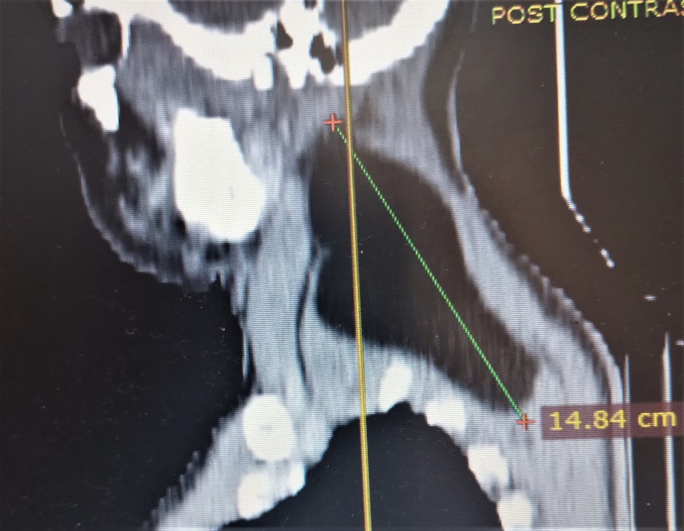

The computed tomogram of the neck showed a hypodense (HU = -109) mass demonstrated in the left paraspinal space of the neck extending from the level of C2 to T1 vertebrae and from posterior to anterior aspect of the neck. It measures about 148 x 97 x 59 mm in its widest craniocaudal, antero-posterior and transverse dimensions respectively (figure, 1 and 2). It shows well outline margin and thin internal septae. There is some enhancement of the septae and the margin of the mass in the post contrast series. No calcification was demonstrated within the mass. There is displacing the adjacent muscles. Anterior displacement of the internal jugular vein and common carotid artery was noted. No intrathoracic extension is demonstrated. No lymphadenopathy is demonstrated. A diagnosis of giant left side neck (paraspinal space) lipoma was made.

Figure 1: Computed tomogram of the neck sagital plane showing a giant fat density mass (lipoma) deep in the posterior aspect of the neck (arrow)

Imaging plays vital role in evaluation of lipoma. Diagnostic imaging employed, include ultrasonography, plain radiography, computed tomography (CT) scan or magnetic resonance imaging (MRI). The cross sectional imaging (CT and MRI) though not readily available has the advantage of assessing the exact location, size and relationship with surrounding structure. [1,2]. They can also help in differentiating benign lipomas from malignant lipomas. On imaging lipomas are well-defined mass of mature fat (adipocytes) and appears as radiolucent on radiographs, low attenuation on CT with Hounsfield Unit (HU) of -65 to -120 (fig, 1 and 2) and hyperintense on T1-weighted MRI. Fine septations can be seen on both CT and MRI. Features that suggest malignancy include thick capsule, ill-defined border, thick or nodular septations, prominent areas of high T2 signal on MRI and prominent areas of enhancement in the post contrast phase [1,2].